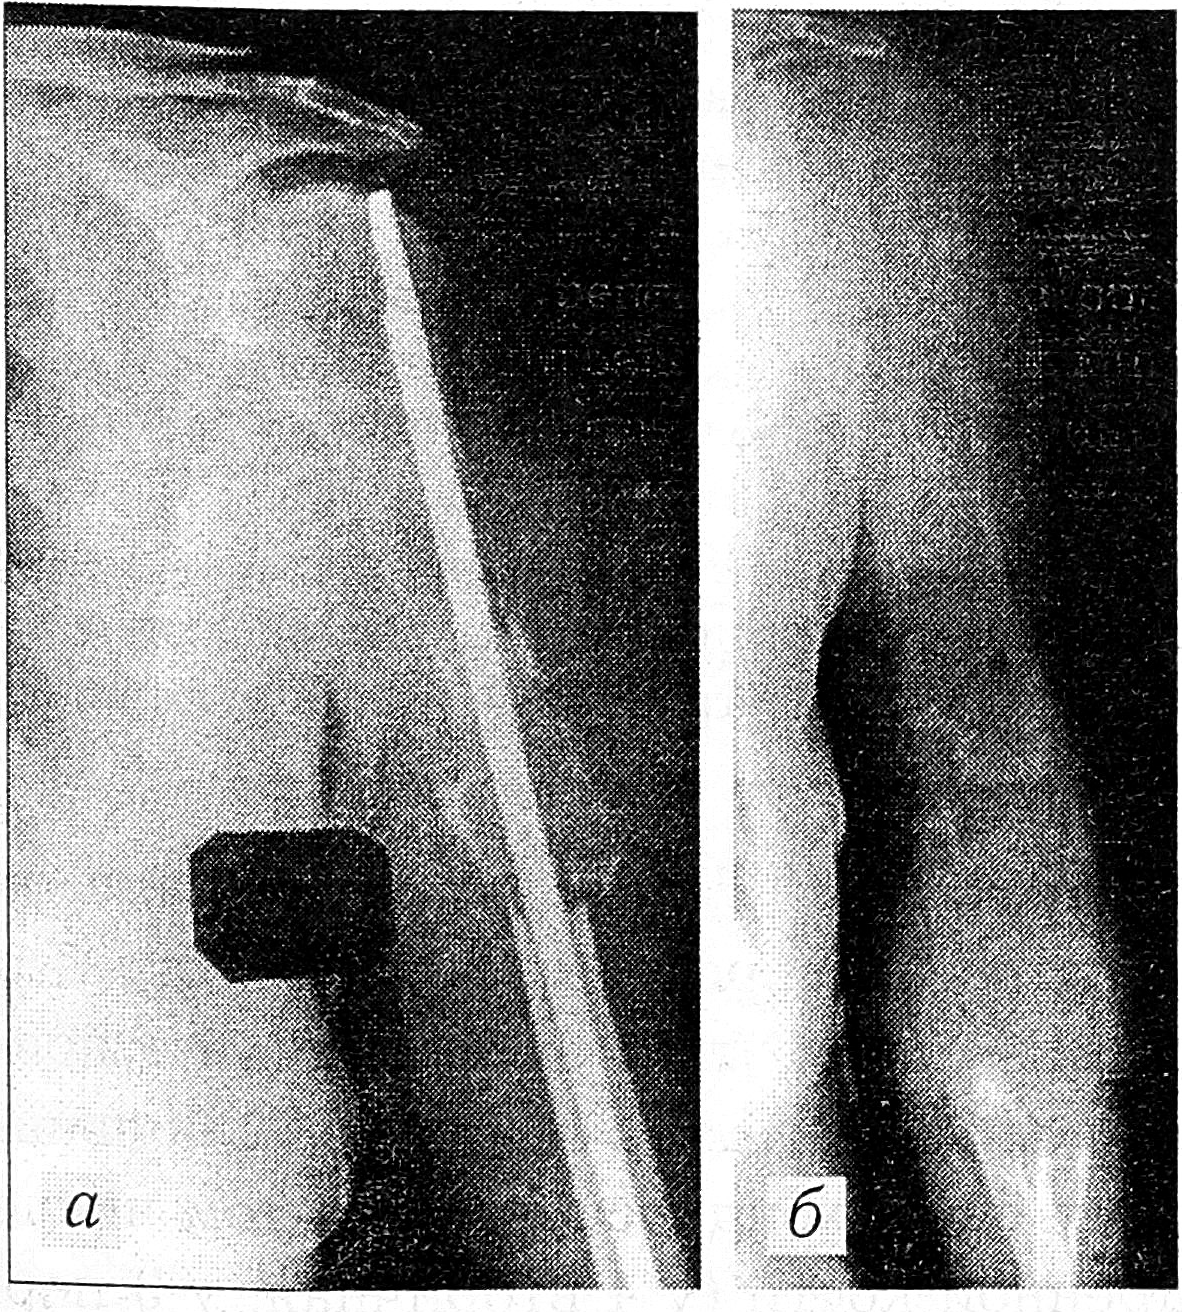

Больная С., 63 лет, находилась на лечении в больнице № 62 с 9.09.77 по 8.02.78 по поводу гипернефроидного рака левой почки, метастаза в левую плечевую кость с патологическим переломом. В июне 1977 г. в травматологическом отделении одной из московских больниц был произведен остеосинтез левой плечевой кости. Консолидации отломков не наступило, сохранились боли. При контрольном осмотре заподозрен патологический характер перелома (рис. 4, а). При обследовании в больнице № 62 диагностирован рак левой почки, и 27.09.77 выполнена нефрэктомия слева (А.Н. Махсон). 15.12.77 произведено тотальное удаление левой плечевой кости с замещением дефекта специально изготовленным эндопротезом из полиамида-12 (рис. 4, б). Послеоперационный период протекал без осложнений. Сразу после заживления раны больная стала активно пользоваться оперированной рукой, выполняла всю домашнюю работу. Гистологическое исследование препарата: метастаз гипернефроидного рака с деструкцией кости. Через 2,5 года наступила дальнейшая генерализация процесса. Выявлены метастазы в других отделах скелета и в легких. Больная умерла через 2 года 9 мес после операции на плечевой кости. Качество жизни в эти последние прожитые ею годы было хорошим: больная не испытывала болей, делала всю домашнюю работу и не ощущала себя инвалидом. Рецидива в области операции на плече не было.

Рис. 4. Рентгенограммы больной С.: a — до операции; б — после тотального удаления плечевой кости с замещением дефекта рентгенопрозрачным эндопротезом из полиамида-12.

Больной Т., 51 года. Диагноз: синовиальная саркома правого бедра с обширным распространением в его верхней половине и вовлечением в процесс бедренной кости (рис. 5, а). 23.04.84 произведена операция: удаление бедренной кости с эндопротезированием дефекта суставом-комплексом Сиваша (рис. 5, б). Разрез кожи и подкожной клетчатки от гребня подвздошной кости вниз по наружной поверхности бедра с переходом на верхнюю треть голени. От большого вертела отсечены сухожилия ягодичных мышц. На расстоянии 30 см от тазобедренного сустава поднадкостнично пересечена бедренная кость (отступя 10 см от нижнего края опухоли). Рассечена капсула тазобедренного сустава и пересечена круглая связка бедра. Головка бедренной кости вывихнута из вертлужной впадины. Путем острой препаровки произведено выделение проксимального отдела бедренной кости с оставлением над опухолью срединной и частично медиальной и латеральной головок четырехглавой мышцы бедра. Вскрыт коленный сустав. Долотом резецированы межмыщелковое возвышение большеберцовой кости и мыщелки бедренной. Костномозговые каналы большеберцовой и бедренной костей рассверлены развертками соответствующего диаметра. Большеберцовый компонент протеза запрессован в большеберцовую кость. Часть разборного диафизарного компонента эндопротеза проведена через костномозговой канал оставшегося участка бедренной кости и соединена с другой частью диафизарного компонента. Чашка эндопротеза запрессована в вертлужную впадину. Эндопротез сомкнут в коленном суставе. Рана послойно ушита наглухо. Гистологическое исследование препарата: синовиальная саркома. Послеоперационный период протекал без осложнений. Рана зажила первичным натяжением. Через месяц больной поднят на ноги. Движения в тазобедренном и коленном суставах лишь слегка ограничены. Через 3 мес ходил с опорой на трость. В течение 2 лет чувствовал себя здоровым, вернулся к прежней работе. При очередном обследовании у больного выявлен бронхогенный рак правого легкого, верифицированный морфологически. В Институте им. П.А. Герцена признан иноперабельным. Рецидива синовиальной саркомы на бедре не отмечалось. Проводилась гамма-терапия, но процесс в легких прогрессировал, и через 2,5 года после операции на бедре больной умер от рака легкого.

Рис. 5. Рентгенограммы больного Т.: а — до операции; б — после тотального удаления бедренной кости с эндопротезированием дефекта протезом-комплексом Сиваша.